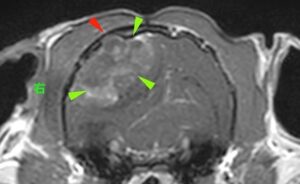

・脳に巨大な腫瘤が認められた

・腫瘤内部は石灰化が疑われた

・腫瘤周囲の骨が一部溶けている所見

MRI画像から上記3点が認められた。

これらの特徴的な所見から髄膜腫が疑われた。